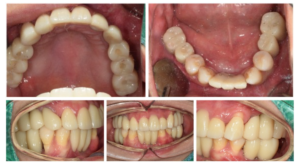

모든 치료가 마무리된

구강 내 사진인데요.

환자분께서는 다수 치아의 상실과

흔들림으로 인해

평소 저작이 잘되지 않아

소화도 안되는 등

불편감이 많으셨는데

치료 후에는 양측 저작이 편안하게 잘 되고,

심미성도 높아져서 만족해하셨습니다.